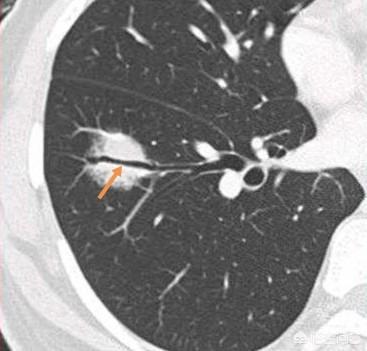

Il s'agit d'un petit nodule sur la plèvre interlobaire, et de tels nodules isolés sur la plèvre interlobaire sont presque toujours bénins et ne suscitent pas d'inquiétude.

L'étape suivante consiste à déterminer la nature bénigne ou maligne des nodules pulmonaires. Les nodules bénins ne sont en aucun cas des ganglions lymphatiques dans les poumons, des tumeurs difformes, des pneumocytomes sclérosants, etc. Les nodules restants sont ceux qui peuvent être bénins ou malins, et le principe général du traitement de ces nodules est de recommander un suivi, avec un délai de révision allant de 3 mois à 1 an, en fonction des spécificités du nodule (morphologie, taille, densité, etc.). Certains nodules peuvent se résorber et disparaître au cours du suivi, comme les nodules inflammatoires, tandis que d'autres peuvent rester inchangés, comme les granulomes, ce qui est une bonne information. Si des signes de malignité apparaissent au cours du suivi, tels que l'élargissement du nodule, l'augmentation des composants réels ou solides dans le nodule de verre dépoli, un nodule plus dense, ou la présence de vaisseaux sanguins périphériques qui se développent, etc. En fait, c'est comme regarder les gens, un visage de droiture est généralement une bonne personne, une mauvaise personne féroce et vicieuse, et certains temporaires ne peuvent être vus que par l'observation du comportement de la personne, si les règles ne sont généralement pas effrayées, et si vous trouvez qu'il y a un mauvais comportement devrait être traité en temps opportun. Figure 1, nodule de verre dépoli dans la partie supérieure du poumon gauche (flèche orange), suivi pendant plus de deux ans sans changement. Figure 2, deux petits nodules de verre dépoli dans la partie supérieure du poumon droit (flèches orange), qui ont disparu après deux ans. Figure 3, nodule en verre dépoli dans la partie supérieure droite du poumon, qui a grossi au cours du troisième suivi, il est recommandé de le traiter positivement, et la pathologie chirurgicale du carcinome in situ, c'est-à-dire des lésions précancéreuses, peut réellement tuer le cancer du poumon dans l'œuf.